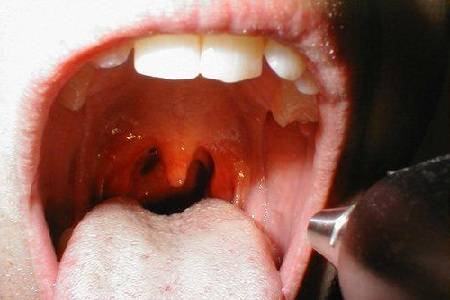

慢性扁桃体炎

正常咽喉慢性扁桃体炎是腭扁桃体的持续性炎症,通常发生在大龄儿童和

慢性扁桃体炎-鉴别诊断